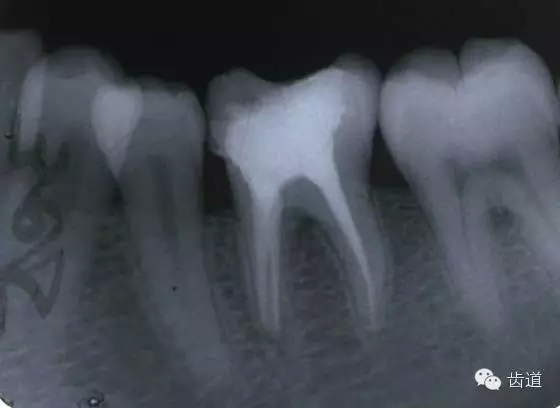

(3)髓室底穿孔:處理方法同上。同時(shí)找到根管口,按常規(guī)進(jìn)行根管預(yù)備和充填。如穿孔范圍太大易導(dǎo)致根分歧病變,予后欠佳??尚懈芡饪啤?/span> (4)根管壁形成臺(tái)階:先換小號(hào)銼去除臺(tái)階,再順序擴(kuò)挫。如根管壁穿孔,找到主根管進(jìn)行預(yù)備后,主根管及側(cè)穿道同時(shí)充填。在根尖1/3或根尖彎曲處側(cè)穿,根充后,配合根尖手術(shù)——根切+倒充填。 (三)髓腔壁穿孔的預(yù)防 1.掌握每個(gè)牙齒的髓腔解剖形態(tài)及其在牙齒表面的投影范圍。 2.術(shù)前拍X線片。 3.進(jìn)行規(guī)范化操作,隨時(shí)與X線片核對(duì)器械進(jìn)入方向及進(jìn)入深度。 器械折斷在根管內(nèi),阻塞根管,妨礙治療操作。如不能取出,使根管治療不能繼續(xù)進(jìn)行,不得不輔以根尖手術(shù)。 左上7近中頰根器械折斷 右上6腭根器械折斷 1.器械本身的原因 材料質(zhì)量欠佳,受力后易折斷。 器械反復(fù)使用,產(chǎn)生折痕,用力后也易折斷。 消毒方法不當(dāng),消毒液中未放防銹劑,器械銹蝕易折。 2.術(shù)者器械使用不當(dāng) 遇有阻力,仍強(qiáng)行進(jìn)入,用力過(guò)大過(guò)猛,超過(guò)了器械所能承受的程度 未按操作要求使用器械(跳號(hào)) 器械在細(xì)窄根管內(nèi)被卡住后,仍勉強(qiáng)旋轉(zhuǎn)器械柄 折斷于根管內(nèi)的器械要盡量取出,若無(wú)法取出經(jīng)常規(guī)充填后,成功率不受明顯影響。 1.折斷器械有一部分露在根管口外,用鑷子或持針器夾取出。 2.器械斷端在根管口內(nèi):用超聲根管銼在該器械旁增隙,通過(guò)超聲震蕩和沖洗,可將折斷器械從根管內(nèi)震動(dòng)沖出。在手術(shù)顯微鏡下直視操作,大大提高了取出的成功率。 3.折斷器械尖端已超出根尖孔:無(wú)癥狀不處理;有疼痛則作根尖手術(shù)取出。 4.折斷器械較長(zhǎng),各種方法均不能取出,可作根管電解消毒,塑化治療或塑化劑處理,根管充填。 若患牙根尖有病變,必要時(shí)作根尖切除+倒充填。 1.使用前認(rèn)真檢查器械有無(wú)生銹、折痕、螺紋松解等現(xiàn)象。 2.嚴(yán)格按器械使用規(guī)則進(jìn)行操作。 3.使用機(jī)用根管器械,應(yīng)支點(diǎn)穩(wěn)、轉(zhuǎn)速慢,并只能應(yīng)用于直的根管。 4.制備開(kāi)髓洞形時(shí),應(yīng)充分暴露根管口,對(duì)彎曲根管能盡量減少其彎曲度,對(duì)彎曲度在30o以上的根管盡量采用超聲根管預(yù)備并使用鎳鈦根管挫。 5.控制器械使用次數(shù):根管銼刃部的鋒利程度隨所預(yù)備的根管數(shù)目增加而降低。 25#以下器械只能用1—2次,30#—50#器械可用二次。 牙折分為冠折、根折及冠根折三種。根管治療后,由于牙折導(dǎo)致拔除者屢見(jiàn),故應(yīng)引起足夠重視。 (一)牙折發(fā)生原因 1.經(jīng)根管治療的牙齒,因失去了牙髓的營(yíng)養(yǎng)而脆性增大。 2.制備開(kāi)髓洞形時(shí),過(guò)多的磨除了牙體組織,削弱了牙體組織強(qiáng)度。 3.根管清理和成形以及做冠樁預(yù)備過(guò)程中,過(guò)多的磨除根管壁,削弱了牙根強(qiáng)度。 4.用牙膠做根管充填時(shí),側(cè)向或垂直壓力過(guò)大,均可造成牙根縱折。 5.其他:根管釘、樁的采用;熱塑冷凝的牙膠尖填入根管后自身體積膨脹;牙周受累的牙齒,支持骨喪失,也增加了牙折的機(jī)會(huì)。 (二)牙折的處理 應(yīng)盡可能保存患牙 1.冠折:根據(jù)折斷的牙體組織的多少及部位,可分別選擇充填;加螺旋釘固位;全冠或樁冠修復(fù)。 2.冠根折:折斷線在齦下不足3mm,配合齦切術(shù)或冠延長(zhǎng)術(shù),將斷端暴露在齦上,然后根據(jù)缺損情況考慮冠修復(fù)的種類。 折斷線在齦下超過(guò)3mm,患牙牙根較長(zhǎng),正畸力將牙根牽引,無(wú)條件做正畸治療的單根牙則拔除,多根牙則可做截根或半切除術(shù)。 3.根橫折:在冠方1/3處理方法同冠根折。 在根中1/3根折線不與牙周袋相通,做根內(nèi)固定,加牙冠部夾板固定4—8周。在根尖1/3,調(diào)合 解除創(chuàng)傷力,如有癥狀做根尖切除術(shù)。 4.根縱折:?jiǎn)胃绖t拔除;多根牙做截根術(shù)或半切除術(shù)。也有報(bào)告,用切開(kāi)翻瓣暴露縱折牙根,粘接劑粘合裂根的方法保留縱折牙牙根,若以后出現(xiàn)牙周袋則拔除。 (三)牙折的預(yù)防 1.根管治療過(guò)程中,有薄壁銳尖或陡峭的無(wú)基釉質(zhì),應(yīng)及時(shí)降低咬合或磨除。根管治療后,常規(guī)調(diào)合。 2.根管治療應(yīng)遵循:在保證治療的前提下,盡量保留健康的牙體組織。 3.根管充填操作用力適度。 五、下唇麻木 (一)發(fā)生原因:主要由下齒槽神經(jīng)損傷所致 1.治療操作中藥物、器械或根充物超出根尖孔,進(jìn)入下頜管損傷下齒槽神經(jīng) 2.解剖因素:下頜牙齒根尖距下頜管太近,有些牙根與下頜管相連,以下頜第二恒磨牙多見(jiàn) 左下7根充后下唇麻木 左下5根管預(yù)備后下唇麻木 (二)處理: 1.根據(jù)病史認(rèn)真查找原因,如為炎癥刺激所致,應(yīng)積極治療根尖周炎,加口服營(yíng)養(yǎng)神經(jīng)藥物。 2.理化刺激所致,口服營(yíng)養(yǎng)神經(jīng)藥物。 (三)預(yù)防: 1.作根管治療前拍X線片,下頜牙齒應(yīng)特別注意與下頜管的關(guān)系。 2.準(zhǔn)確測(cè)量根管工作長(zhǎng)度,各種操作均在工作長(zhǎng)度范圍內(nèi)進(jìn)行。根管封藥不可過(guò)飽和,防止藥液溢出根尖孔。 此種意外發(fā)生,給患者帶來(lái)很大的精神壓力,如器械落入呼吸道,則增加更大的痛苦,應(yīng)慎重處理。 (一)發(fā)生原因 1.術(shù)者精神不集中 2.患者過(guò)于緊張不合作 3.患者體位不正確 4.器械從手中滑脫 (二)處理 1.醫(yī)護(hù)人員應(yīng)鎮(zhèn)靜,安撫患者。 2.立即拍腹部平片。 3.落入消化道應(yīng)住院觀察。 4.服用長(zhǎng)纖維及有潤(rùn)滑作用的食物,勿服瀉藥。 5.適當(dāng)走動(dòng),勿劇烈運(yùn)動(dòng)。 6.每天拍腹部X線片,檢查大便至排出。 7.落入呼吸道,應(yīng)請(qǐng)耳鼻喉科或胸外科醫(yī)生協(xié)助取出。 (三)預(yù)防: 1.針對(duì)原因預(yù)防。 2.治療時(shí)上橡皮障。 3.無(wú)條件用橡皮障,可在器械柄拴安全鏈。 皮下氣腫是根管治療中少見(jiàn)的并發(fā)癥 (一)臨床表現(xiàn) 根據(jù)患牙的部位不同,可分別出現(xiàn)在頰部、頸部、和眶周等疏松軟組織迅速腫脹、充血,有捻發(fā)音。捻發(fā)音是組織氣腫的病理特征,以此和其他腫脹做鑒別。如空氣向頸部移動(dòng)可引起呼吸困難。 (二)發(fā)生原因 1.用壓縮空氣吹干根管時(shí)間過(guò)長(zhǎng)。 2.使用過(guò)氧化氫液沖洗根管,將藥液壓出根尖孔。 不可加壓??! (三)處理 一般不需特殊治療,給予抗生素預(yù)防感染 上頜竇曲霉病、上頜竇疼痛、上頜竇炎癥等。 根管治療的各種并發(fā)癥,絕大多數(shù)情況是由術(shù)者操作不規(guī)范所致。在根管治療過(guò)程中,術(shù)者應(yīng)嚴(yán)格按照規(guī)程進(jìn)行每一步操作,這些并發(fā)癥是完全可以避免的。